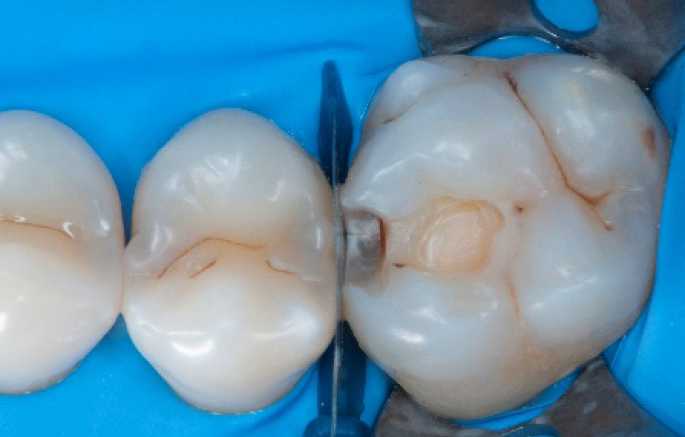

Initial situation of the patient

The patient came for a routine control appointment. She didn‘t report any symptoms but some bleeding during brushing.

Initial situation: an old class I composite restoration on 1.6. New caries on the mesial wall. Presence of plaque and inflammation.

• On the x-ray examination, a mesial translucency (initial caries) was found on tooth 1.6.

• The tooth presented an old class I composite restoration.

• Marginal inflammation and plaque were present.

• No symptoms were referred by the patient.